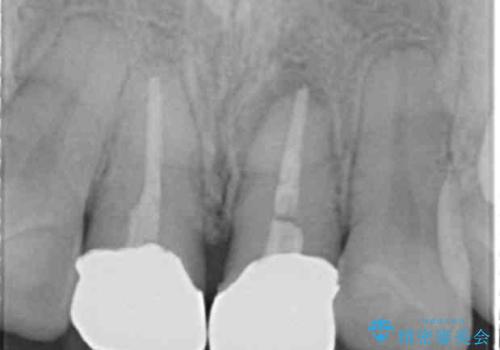

- 「幼少期に転んで治療した前歯がうずく、疲れると膿が出る。」と治療を希望され来院されました。

X線写真検査に加え圧痛、打診痛が認められたため、慢性根尖性歯周炎と診断し、根管治療から行うセラミック治療を計画します。